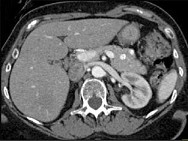

- 单项选择题根据所提供的图像,最可能的诊断是 ( )

A、胰腺癌

B、胰岛细胞瘤

C、病理性脾动脉硬化

D、假性囊肿

E、以上都不是